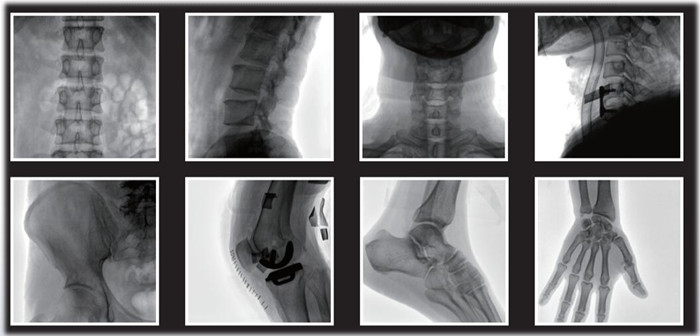

1)小C,骨科手術必備設備,也被稱為骨科小C。作為骨科醫(yī)生的眼睛,能在手術中透視實現(xiàn)準確定位,輔助醫(yī)生順利、快速、高效完成手術。目前,小C在我國普及率極高,基本上所有二級及以上醫(yī)院都標配小C。

小C在骨科的應用是全方位的

2)中C,學名外周介入C形臂(Peripheral Interventional C-Arm)。與小C相比,中C不僅大幅提高了X射線系統(tǒng)功率,更重要的是增加了減影等血管機相關功能,基本可以完成80%的介入手術需求,主要應用在周圍血管科、消化內(nèi)科、婦科、整形科等領域。